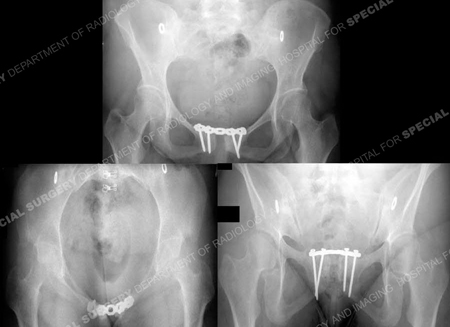

Diagnostic work-up included standard radiographs of the pelvis demonstrating widening of the symphysis pubis of 9 cm and opening of both sacroiliac (SI) joints posteriorly. A CT scan using 2 mm thin cut technique was performed to evaluate the posterior pelvic ring and SI joints. The CT scan demonstrated bilateral sacroiliac joint disruptions. In addition, a MRI scan documented disruption of the pelvic floor and extensive hematoma. Imaging studies revealed an unstable pelvic dislocation with significant symphyseal widening and disruption of the posterior pelvis equivalent to an APC III, or Tile Type C pelvic injury. Open reduction and internal fixation (ORIF) of the pubic symphysis was performed with placement of a contoured 5-hole 3.5 mm pelvic reconstruction plate and screws. Anatomic reduction and stabilization of SI joints were performed using bilateral posterior ilio-sacral screw arthrodesis. Under fluoroscopic control bilateral single 7.3 mm cannulated screws were inserted percutaneously into the body of S1. The perioperative course was unremarkable. She followed up at regular intervals and reported progressive resolution of pain symptoms. The SI screws were removed at 2 years due to mild radiographic evidence of screw loosening. She returned at 2.5 months following hardware removal and reported complete pelvic pain relief and return to pre-injury activities.

The patient returned at 25.5 months following initial surgery (and 2.5 months following hardware removal) with excellent clinical and radiographic results including a return to pre-injury physical activity.